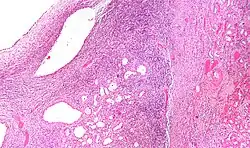

Micrograph of a cystic nephroma. H&E stain.

The characteristics of cystic nephromas are:

- Cysts lined by a simple epithelium with a hobnail morphology, i.e. the nuclei of the cyst lining epithelium bulges into the lumen of the cysts,

- Ovarian-like stroma that has a:

- Spindle cell morphology, and has a

- Basophilic cytoplasm.